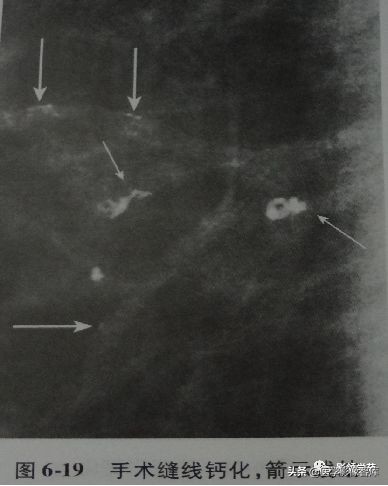

3. Suture calcifications

代表手术后缝线的钙化,典型表现为线样或管状,并常可见线结。